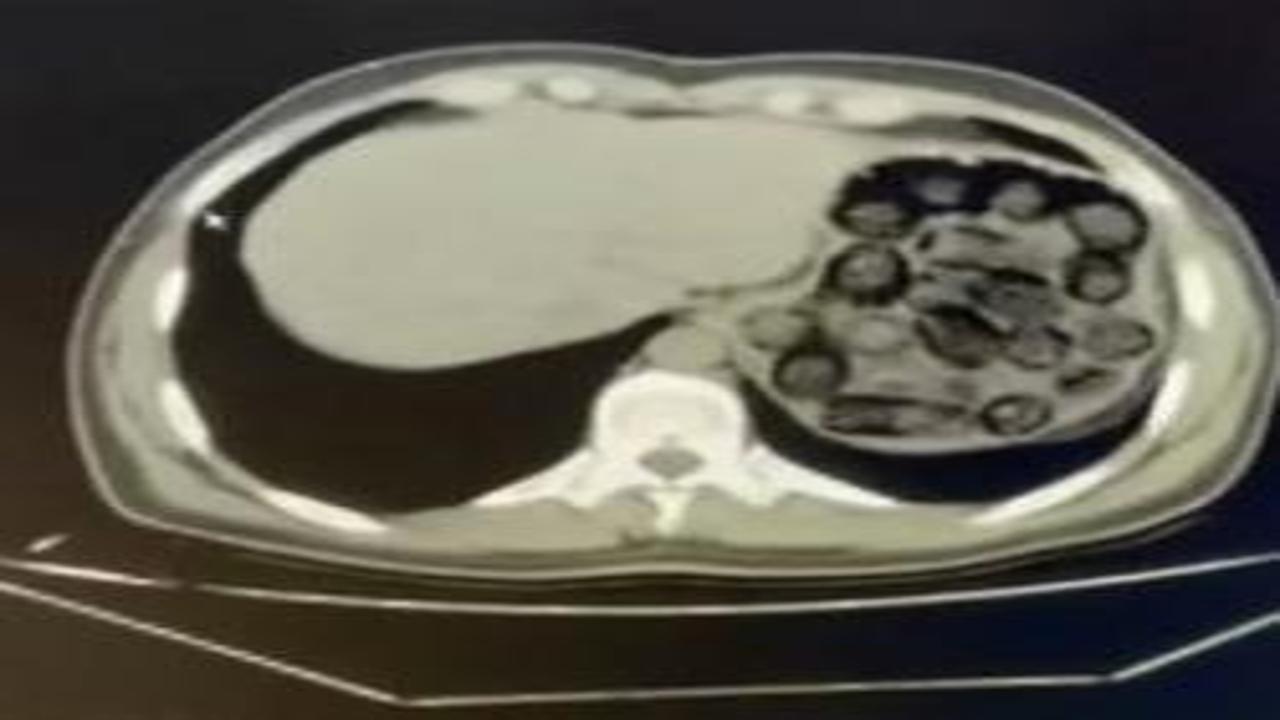

İranlı şüphelilerin mide ve bağırsaklarından 91 kapsül metamfetamin çıktı

Diyarbakır'da polisin takibe aldığı İran uyruklu iki şüphelinin hastanedeki kontrollerinde, mide ve bağırsaklarında 807 gram uyuşturucu taşıdıkları belirlendi.